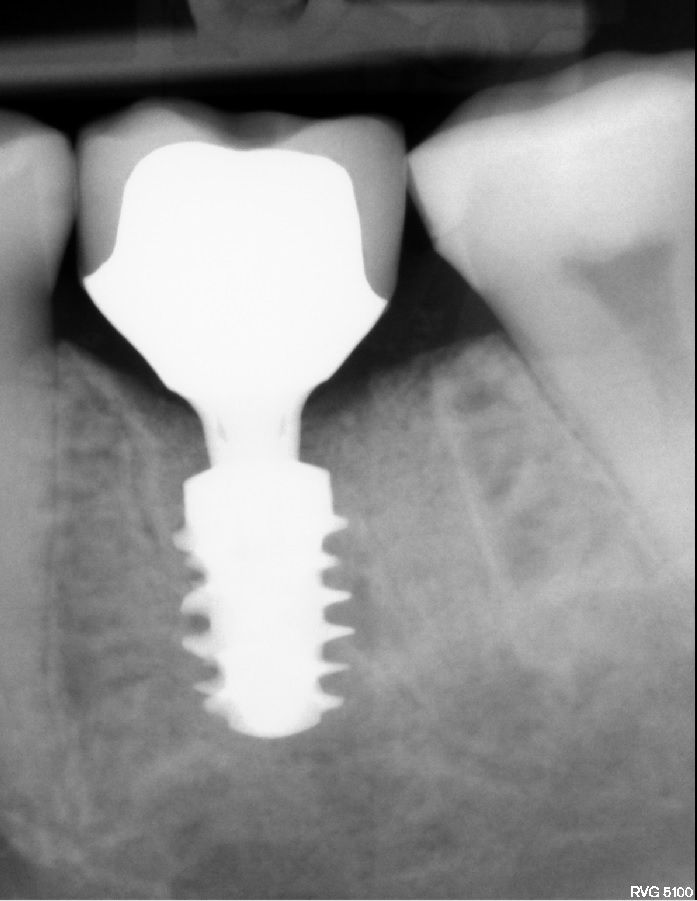

#36 牙的手术过程从局部麻醉和下牙槽神经阻滞开始。通过分割磨牙根实现无翻瓣反射的无创拔牙;从而保留肺泡壁和根间隔膜(图3-4)。仔细清洁牙槽,形成种植体路径并放置Straumann ® BLX 种植体 5.5 x 8 mm (图 5-7)。为了促进非浸没式愈合,将标准愈合基台连接至种植体。骨壁和种植体之间的间隙填充有同种异体骨材料颗粒(maxgraft®,botiss 生物材料,德国)。应用富含血小板的纤维蛋白(PRF)来实现适当的初步愈合。调整软组织边缘并用聚丙烯 6/0 缝合,使愈合基台暴露(图 8-9)。将粘性牙周Reso-Pac ®敷料(来自德国杜伊斯堡的Hager & Werken)放置在治疗区域上以协助愈合过程(图10)。

手术后一周,拆线(图11-12)。在同一次就诊时,拍摄了垂直牙科射线照片(图 13),显示种植体处于正确的修复位置。四个月后,愈合基台被移除。粘膜外观表明植入物周围有稳定且健康的软组织,具有足够的生物宽度和光滑的出现轮廓(图14-15)。取印模,一个月后,将最终的氧化锆陶瓷牙冠拧到种植体上(图 16-18)。